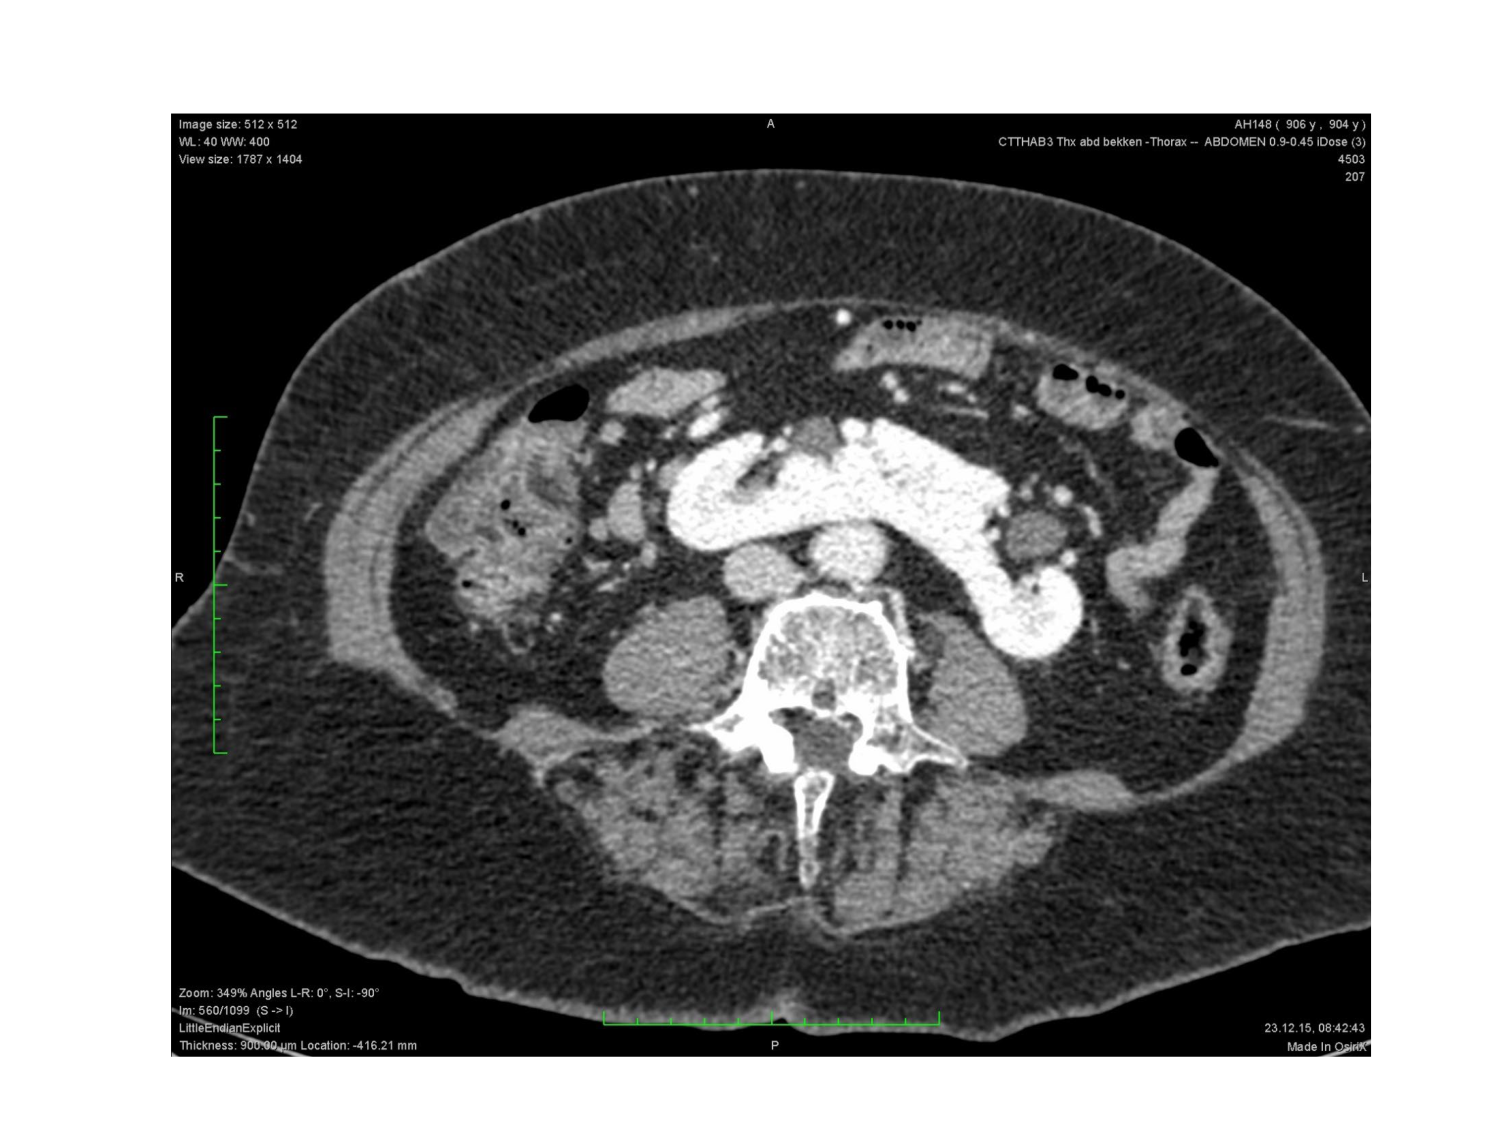

11.47 · Rein, voies urinaires et retropéritoine

Rein, voies urinaires et retropéritoine